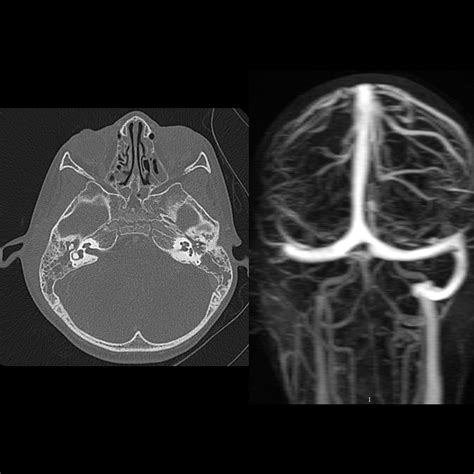

Computed Tomography Venography (CTV)

CTV is another non-invasive imaging technique that uses computed tomography (CT) to visualize the venous sinuses. It involves the injection of a contrast agent to enhance the visibility of the venous sinuses. CTV can detect abnormalities such as thrombosis, aneurysms, or tumors and is particularly useful in patients with suspected CVST or traumatic injury to the SSSV.

Digital Subtraction Angiography (DSA)

DSA is an invasive imaging technique that involves the injection of a contrast agent into the arterial system. It provides detailed images of the cerebral vasculature, including the SSSV. DSA is particularly useful in patients with suspected aneurysms or arteriovenous malformations (AVMs) involving the SSSV. However, it is an invasive procedure and carries a risk of complications, such as stroke or hemorrhage.